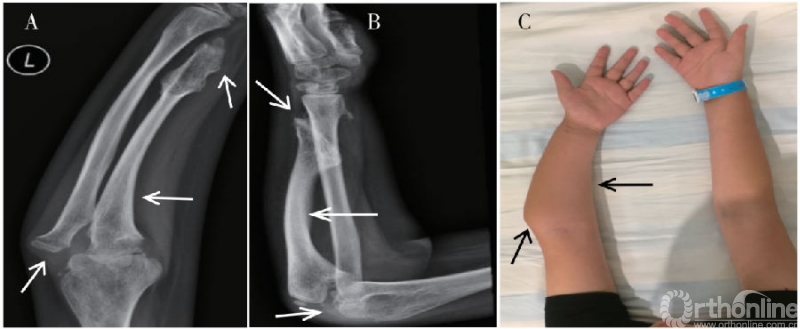

前臂畸形导致外观异常是患儿就诊的主要原因。30%-60%的MHE患者出现不同程度的前臂畸形,出现尺骨生长迟缓、尺桡骨弯曲、下尺桡关节脱位等一系列病理改变,临床表现为尺骨短缩,腕、肘关节畸形和活动障碍(图1)。

图1. 典型多发性遗传骨软骨瘤病患者